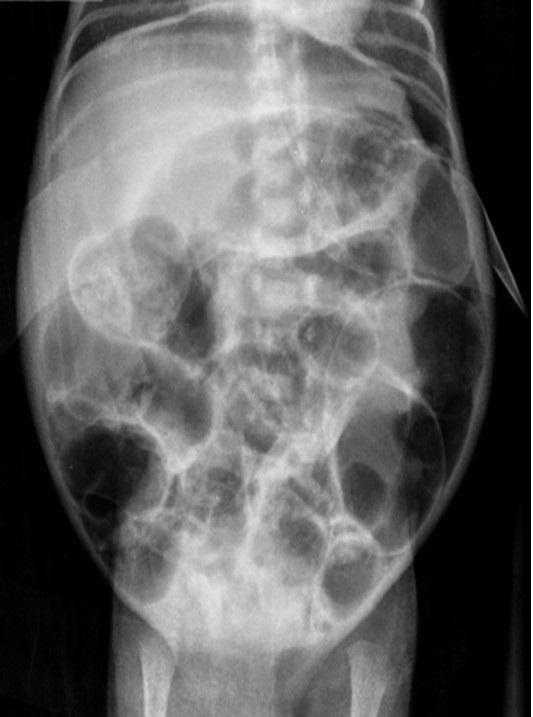

At 30 days of life, the baby developed an ill appearance, dark brown secretions from the orogastric tube, abdominal distension, increased abdominal girth, and a tender abdomen. Laboratory investigations showed raised white blood cell (WBC) counts of 12.8 x 103/L, C - reactive protein (CRP) 8.1 mg/L, Procalcitonin (PCT) 14ng/ml, and blood culture Staphylococcus haemolyticus. An abdominal x-ray revealed pneumoperitoneum (Fig. 1). Laparotomy showed a 0.5 cm perforation on the anterior aspect of the first part of the duodenum (Fig. 2) covered by fibrinous tissue and adhered to the inferior surface of the liver. Primary closure of the perforation was performed using 5-0 poliglecaprone and a Penrose drain was placed. Orogastric and orojejunal tubes were placed. On the third postoperative day (POD), the drain was removed followed by extubation. On POD-5, trophic enteral feeds were started via orojejunal tube and increased as per acceptance. At POD-15, the baby developed severe respiratory insufficiency which caused cardiac arrest and warranted intubation with advanced CPR but the baby succumbed.

Figure 1

Abdominal x-ray showing pneumoperitoneum.